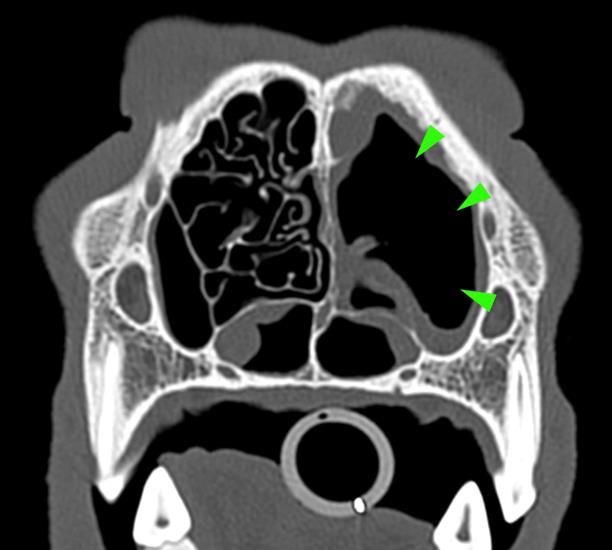

A 3-year-old Siberian husky was presented for chronic nasal discharge. A CT scan of the head showed marked loss of turbinates in the rostral aspect of both nasal cavities, more severe on the left side (green arrowheads).